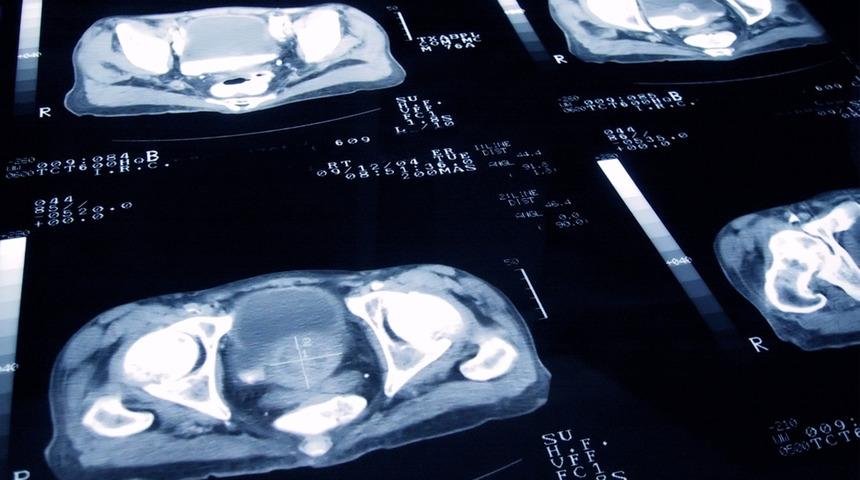

Prostat ameliyatı yapılırken en çok tercih edilen teknik olan Holep, lazer yardımıyla gerçekleştiriliyor. Vücutta daha az travmaya neden olan başarılı ameliyatları beraberinde getiren Holep tekniğinin avantajları bunlarla da sınırlı değil. Holep, daha az kanama sebep oluyor ve prostatın sinirlerine zarar vermeden ameliyat gerçekleştiriliyor.

Prostat, mesane ve böbrek kanseri gibi hastalıkların yaygın olması konuyla ilgili araştırmaları da beraberinde getiriyor. Farklı ekiplerle birleşerek üroloji ile ilgili fikir alışverişinde bulunduklarını aktaran Yıldırım, "Holep'li ameliyat prostat ameliyatında son zamanlarda en çok kullanılan ve dünyada en çok tercih edilen başarılı bir tekniktir. Bu ameliyat tekniği prostatın sinirlerine zarar vermeden, kanamadan daha az hastanede kalarak daha az vücudun travma görmesiyle yapılabilen başaralı bir ameliyat şekli” diye konuştu.

Yıldırım, ayrıca ürolojinin ileri ameliyat tekniklerinin yaygın olarak kullanıldığını belirterek, “Radikal prostat kanser ameliyatları radikal sistostomi gibi mesane kanserinin büyük amaliyatları veya böbreğin kanser ameliyatları gibi onkolojik ameliyatlardan böbreğin tamamını lorkospi ile alınması veya böbreğin bir parçasını parsel alınması gibi onkolojik ameliyatlarda yapılıyor” dedi.